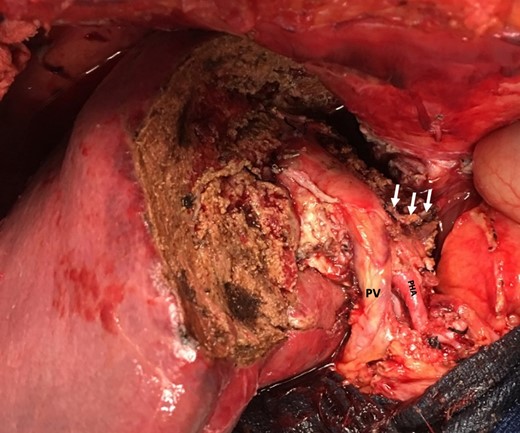

Intraoperatively, the surface of the liver was noted to be quite inflamed. There were dense pericholecystic adhesions, and the gallbladder was diffusely thickened. A hard mass with surrounding inflammatory and fibrotic changes was encountered in segment IV. After mobilizing the liver and controlling all hilar structures, in addition to Doppler confirmation of right hepatic artery flow, an extended left hepatectomy was performed. The right hepatic artery was carefully dissected off the mass, and the left liver including segments 5 and 8 as well as the caudate lobe was resected (Fig. 4). We were able to preserve the main bile duct. Pathology subsequently revealed XGC extending into the hepatic parenchyma (Fig. 5). After an uneventful post-operative course patient was discharged to extended care facility in stable condition 8 days after his surgery.

Remnant liver after left extended hepatectomy with preserved hilar structures (portal vein (PV), proper hepatic artery (PHA) and staple line after resection of left portal vein (arrows)).